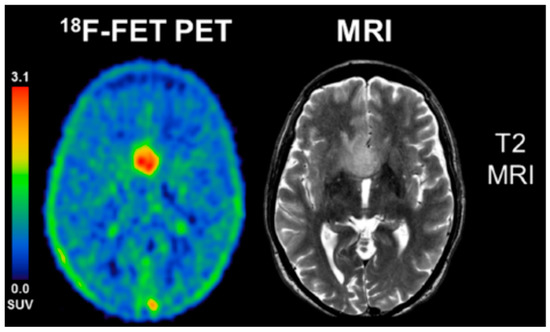

- Galldiks, N.; Schroeter, M.; Fink, G.R.; Kracht, L.W. Interesting image. PET imaging of a butterfly glioblastoma. Clin. Nucl. Med. 2010, 35, 49–50. [Google Scholar] [CrossRef] [PubMed]